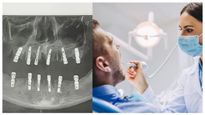

ஒரே நாளில் 23 பற்கள் பிடுங்கப்பட்ட சீன நபர் மாரடைப்பால் மரணம்!

பற்களில் உள்ள மஞ்சள் கறையை போக்கணுமா? இதோ வீட்டு வைத்தியம்... இதை ட்ரை பண்ணுங்கள்..!

உங்கள் பற்களில் இருந்து இரத்தம் மற்றும் வாய் துர்நாற்றம் வருகிறதா? அப்போ இதை ட்ரை பண்ணுங்கள்..!

பல் பிரச்சனையா? தினமும் 2 நிமிடம் இப்படி துலக்குங்கள்..!

இந்த கோடைகால தவறுகள் உங்கள் பல் ஆரோக்கியத்தை பாதிக்கும்.. இதை மட்டும் செய்யாதீர்கள்..!

உங்க பல் வெள்ளையாக இருக்கணுமா? இதோ சில வீட்டு குறிப்புகள்.. ட்ரை பண்ணுங்கள்..!

உங்கள் குழந்தைக்கு பல் சொத்தை உள்ளதா? தடுக்க இந்த விஷயங்களை செய்யுங்கள்!

உங்க பற்கள் பால் போல வெள்ளையா பளபளன்னு இருக்கணுமா? அப்ப 'இந்த' 7 டிப்ஸை ஃபாலோ பண்ணுங்க..!

தெரியாம கூட இத பண்ணதுக்கு அப்புறம் பல் விலக்கிராதீங்க... இல்லனா உங்க பல் ஆரோக்கியம் மொத்தமாக போயிரும

உங்க குழந்தைக்கு பல் முளைக்கிறதா? அப்ப வெண்ணிலா சாற்றை இப்படி யூஸ் பண்ணா போதுமாம்!